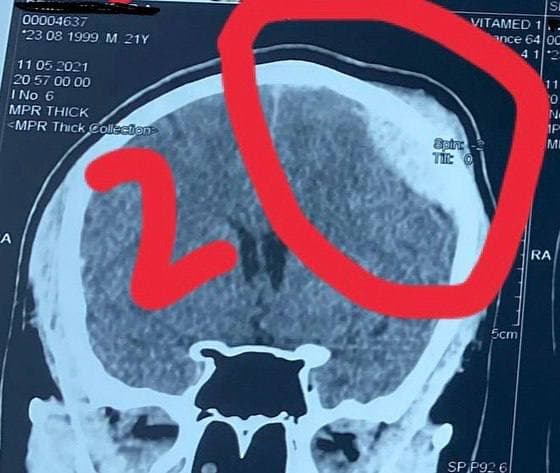

Пострадавший ударился головой и сломал череп. Его доставили в больницу, где экстренно удаляли эпидуральную гематому (скопление крови между внутренней поверхностью черепа и наружным слоем твердой мозговой оболочки в голове). Теперь парню придется ходить с пластиной 50х50мм в голове, которую должны установить в ближайшие три месяца.